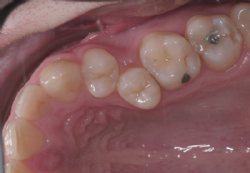

Gar nicht so selten ist die Anzahl der vorhandenen bleibenden Zähne größer als es dem Platzangebot des Kiefers entspricht. In diesen Fällen ist die Entfernung bleibender Zähne oft die einzig zielführende Möglichkeit, harmonische und schöne Zahnreihen zu erhalten. Entfernt werden jene Zähne, deren funktionelle Wichtigkeit relativ am geringsten ist, unter Berücksichtigung etwa vorhandener (behandelter oder unbehandelter) Karies, sowie der geplanten Zahnbewegungen.

Bei geringem Platzmangel kann stattdessen auch die Verschmälerung mehrerer bleibender Zähne des betreffenden Kiefers durchgeführt werden (Approximale Schmelzreduktion, „Stripping"). Dabei werden die Zähne an ihren jeweiligen Berührungsflächen mit geeigneten Instrumenten (feine rotierende Instrumente oder abrasive Streifen) bearbeitet und geringfügig Substanz reduziert.